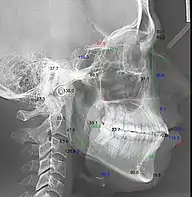

Телерентгенография с цефалометрическим анализом

Цефалограмма — это геометрическая обрисовка телерентгенограммы для изучения абстрактных закономерностей — угловых и линейных кефалометрических параметров.[3][4]